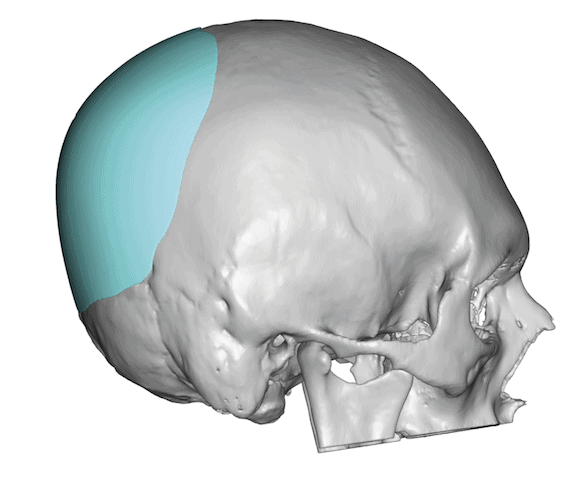

Desire for change of head shape from front view form an inverted V shape to a rounder and wider head shape.

Placement of custom extended forehead-temporal implants through incisions in the crease behind the ear. (he had a prior back of head skull implant which is green in the implant designs and which the head widening implants partially covered it)

Desire for change of head shape from front view form an inverted V shape to a rounder and wider head shape.

Placement of custom extended forehead-temporal implants through incisions in the crease behind the ear. (he had a prior back of head skull implant which is green in the implant designs and which the head widening implants partially covered it)